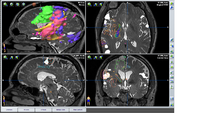

Document, understand, and improve visualization of functional mapping data for intraoperative use

• Understand visualization conventions of functional mapping data for presurgical planning and intraoperative navigation

Iplan

OR Navigation System - Brainlab